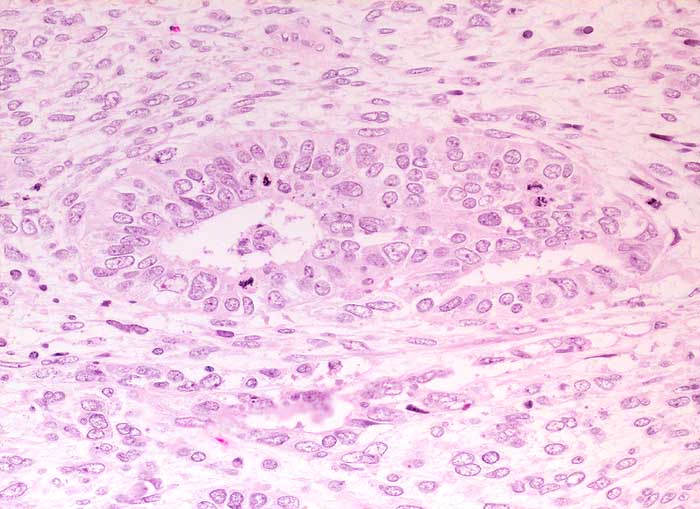

PathoPic – image database / PathoPic ID 6291 - Adenosarkom

Adenosarkom

Mehrreihige Drüse ausgekleidet von Müllerschem Epithel vom proliferativen endometrioiden Typ mit mehreren Mitosen. Das angrenzende Stroma ist sehr zellreich und polymorph.

Im Gegensatz zum Karzinosarkom liegen die Drüsen des Adenosarkoms einzeln in einem zellreichen sarkomatösen Stroma und bilden keinen zusammenhängenden offensichtlich malignen Tumor. Die Drüsenepithelien können jedoch Atypien und Zeichen der proliferativen Aktivität aufweisen.